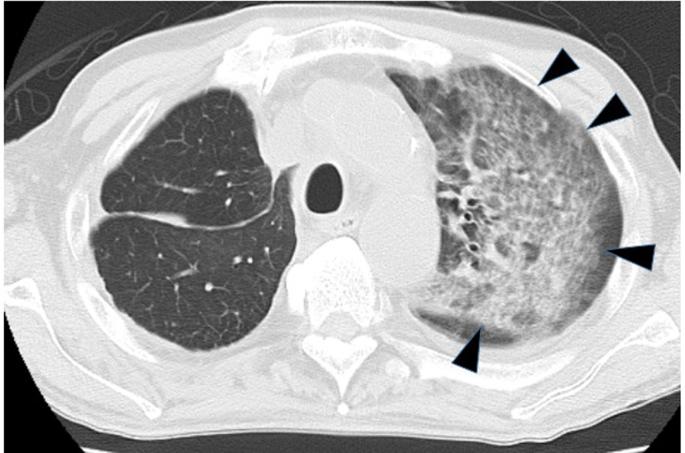

Recent therapeutic advancements have prolonged the survival duration of patients with metastatic or recurrent colorectal cancer even during salvage treatment. Although treatment with regorafenib and trifluridine/tipiracil combination has exhibited apparent survival benefits, clear and objective evidence of a response to these drugs is scarce. Herein, the present study reports the case of a patient with rectal cancer refractory to multiple surgical interventions and standard chemotherapy. Treatment with regorafenib resulted in immediate improvement of respiratory failure caused by pulmonary lymphangitic carcinomatosis. This improvement persisted for over 3 months and was confirmed by radiology. Our findings suggest that regorafenib can reduce peritumoral edema via its interaction with the vascular endothelial growth factor receptor. Thus, regorafenib functions as a multityrosine kinase inhibitor to alleviate symptoms of lymphangitic carcinomatosis despite the low potency of the drug.

近期的治疗进展延长了转移性或复发性结直肠癌患者的生存期,即使在挽救治疗期间也是如此。尽管瑞戈非尼和曲氟尿苷/替匹嘧啶联合治疗已显示出明显的生存获益,但关于这些药物反应的明确客观证据却很少。在此,本研究报告了一例直肠癌患者,该患者对多种手术干预和标准化疗均耐药。瑞戈非尼治疗使由肺淋巴管癌病引起的呼吸衰竭立即得到改善。这种改善持续了3个多月,并得到了放射学证实。我们的研究结果表明,瑞戈非尼可通过与血管内皮生长因子受体相互作用来减轻肿瘤周围水肿。因此,尽管瑞戈非尼药效较低,但它作为一种多酪氨酸激酶抑制剂可缓解淋巴管癌病的症状。